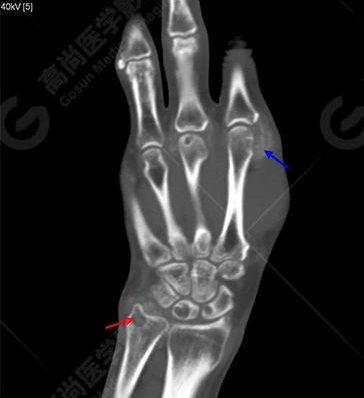

平掃CT:

紅色箭頭提示骨質(zhì)侵蝕囊變;

藍(lán)色箭頭提示踝關(guān)節(jié)滑囊內(nèi)、肌腱內(nèi)多發(fā)稍高密度結(jié)節(jié)影。